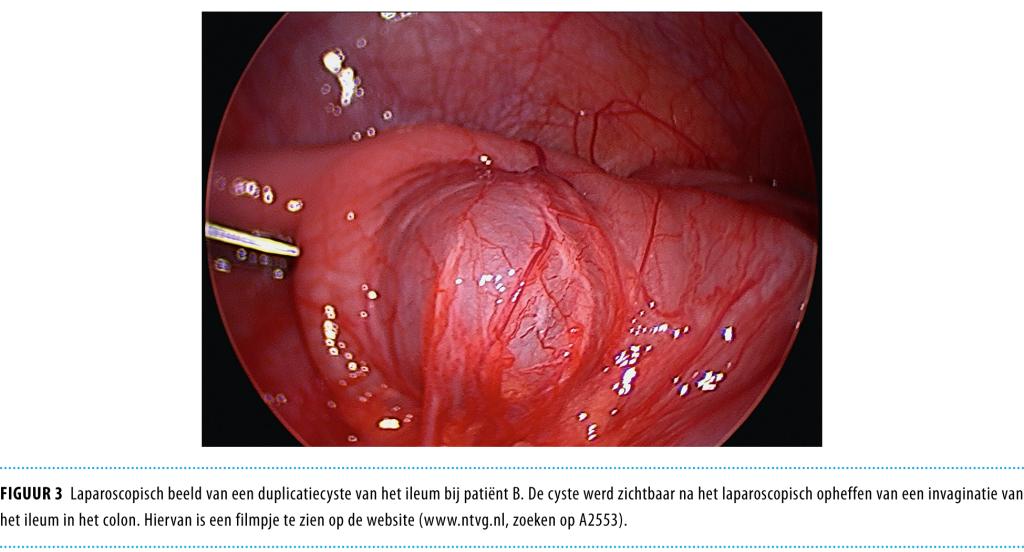

Een 5-jarige jongen werd gezien voor een second opinion vanwege episoden van hevige abdominale pijnklachten en een wisselend bolle buik. Echografisch onderzoek liet een afwijking zien verdacht voor een duplicatiecyste in het terminale ileum. Er werd een laparoscopisch geassisteerde resectie uitgevoerd, waarna de diagnose ‘duplicatiecyste’ bevestigd werd door histologisch onderzoek. Een aantal maanden later werd een 10-jarige jongen gezien met buikpijnklachten, diarree en braken. De abdominale echografie liet een invaginatie zien tot halverwege het colon transversum, alwaar een grote cyste-achtige structuur met vloeistofspiegel aanwezig was. De invaginatie werd laparoscopsisch opgeheven en er volgde een resectie van een duplicatiecyste van het ileum. Een duplicatiecyste van de darm is een zeldzame diagnose (prevalentie 1: 4500), maar het is belangrijk van het bestaan af te weten. Laparoscopie is een elegante manier voor resectie van de duplicatiecyste bij kinderen.